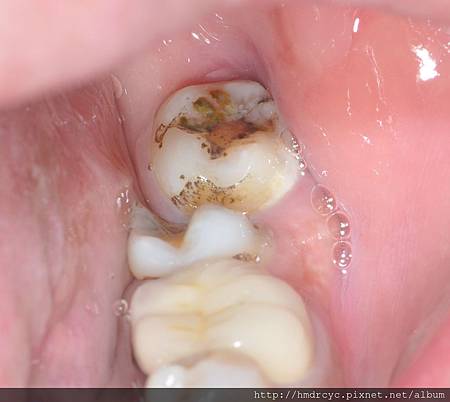

而牙肉包住的地方會牙肉發炎牙周病

因為智齒沒有必要功能

卻容易造成前面牙齒蛀牙或牙周病

所以我們考慮的並不是智齒有沒有用

而是智齒會不會造成災難

如果為了留下一顆沒用的牙齒

卻會害最重要的牙齒蛀牙牙周病

真的要拔除時

可能兩顆都已經壞掉

牙醫建議智齒拔除就不難理解了